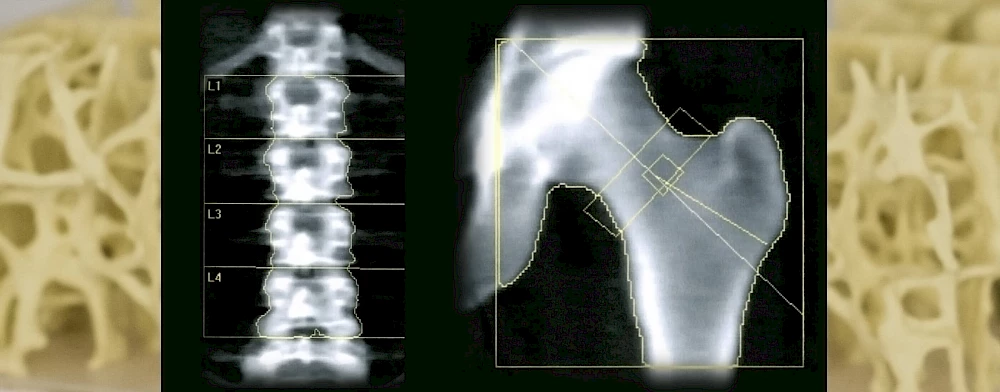

Das Messverfahren der DXA ist entsprechend den Leitlinien das am besten anerkannte Verfahren für die Messung der Knochendichte beim Menschen. Es liefert Informationen über den dreidimensionalen Knochenaufbau und die Festigkeit des Knochens. Die Biegung und die Brechung können hiermit vorhergesagt werden.

Es werden in der Regel immer die linke Hüfte und die Wirbelsäule in einer Messung gemessen und anschließend in Knochendichtemesswerte in g/cm3 umgerechnet. Am wichtigsten sind jedoch die Vergleichswerte, die sogenannte T- oder Z-Werte, die die Knochendichte der untersuchten Patient*Innen in Vergleich mit der Altersgruppe setzen.